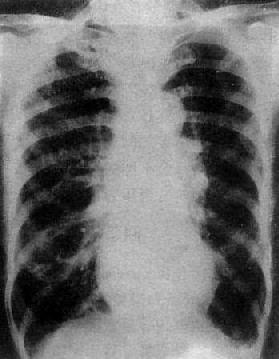

X线表现(图3-2-16),二尖瓣回流较轻,心代偿功能良好时,心大小和形状无明显改变,仅见左心房和左心室轻度增大,当二尖瓣回流在中度以上,心肌代偿功能较差时,则左心房明显增大,在心室也增大,透视下可见左心室收缩时因瓣膜关闭不全而左心房有强烈的搏动。肺有瘀血,右心室亦可增大。主动脉球正常或略小。

二尖瓣关闭不全并狭窄

图3-2-16 二尖瓣关闭不全并狭窄

心增大呈二尖瓣型,右心室增大,肺动脉

段突出,左心耳增大,有肺瘀血